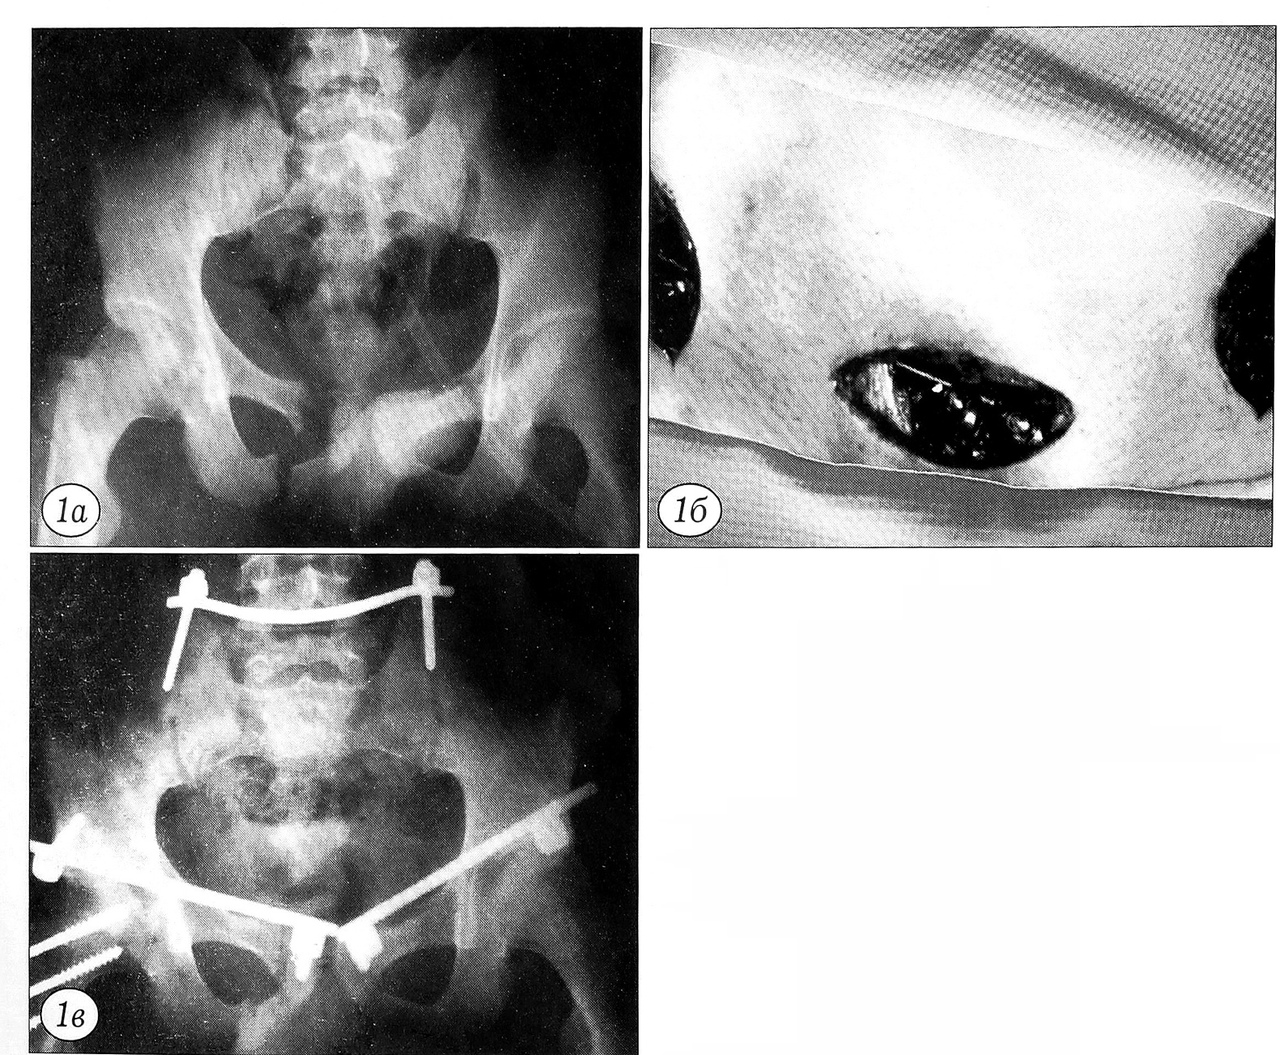

Делали разрез кожи, подкожной жировой клетчатки и фасций над передней нижней подвздошной остью на стороне повреждения и лонным симфизом длиной 1,5~4 см каждый. Расслаивая мышцы, вкручивали винты. На стержни винтов помещали прижимные шайбы и гайки. Корнцангом формировали подкожный канал, соединяющий места введения винтов, так, чтобы бедренные вена, артерия и нерв оказались ниже, а семенной канатик у мужчин (круглая связка у женщин) — выше него. Через канал подкожно проводили стержень, концы которого помещали в прижимные шайбы. Используя внешнее репозиционное устройство, устраняли смещения отломков, после чего систему жестко фиксировали гайками (рис. 1).

Рис. 1. Пострадавший 19 лет с абсолют но нестабильным повреждением таза: закрытым переломом ветвей обеих лонных костей, разрывом левого крестцово-подвздошного сочленения, переломом правой боковой массы крестца. Произведена фиксация внутренней стержне вой системой. а — рентгенограмма таза при поступлении больного в клинику; б — внешний вид внутренней стержневой системы после стабилизации переднего полукольца; в — рентгенограмма таза после выполнения внутренней стержневой фиксации.